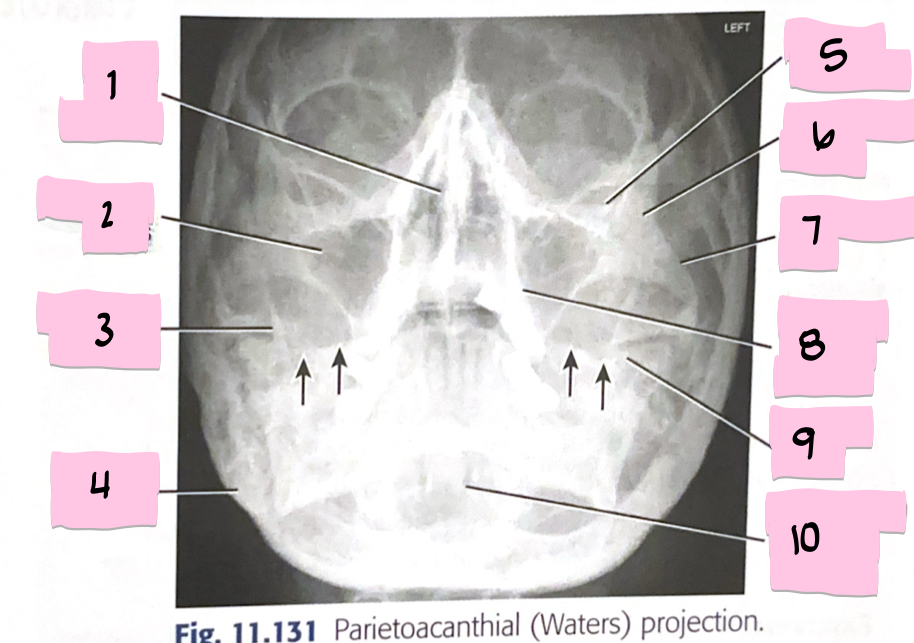

What is 1 pointing to?

Inferior orbital margin

What is 2 pointing to?

Maxillary sinus

What is 3 pointing to?

Petrous ridge

What is 4 pointing to?

Frontal sinuses

What is 5 pointing to?

Bony nasal septum

What is 6 pointing to?

Petrous ridge